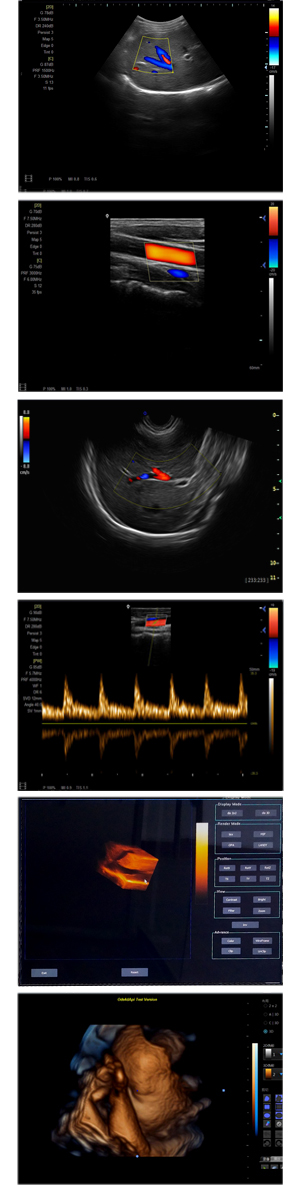

XF-7500型,秉承先鋒彩超技術(shù)之精華,擁有高雅大氣的獨特外型,為最新一代應用型數(shù)字彩色多普勒診斷系統(tǒng),魅力與實力相融合??蓮V泛適用于腹部、婦產(chǎn)科、心臟、小器官、乳腺、肌骨及外周血管等諸多方面的診查,讓您在臨床超聲診斷應用領(lǐng)域得心應手,綻放異彩!

● 3D/ 4D成像技術(shù)/選配

● 應用于腹部、腎臟、泌尿系統(tǒng)、產(chǎn)科、婦科、盆腔、大動脈、肌肉組織、小器官、乳腺、心臟等

● 能量多普勒成像(PDI)

● 彩色血流量圖(CDE)

● 脈沖頻譜多普勒成像(PW)